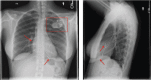

Initial efforts to artificially stimulate the heart were borne out of a necessity to prevent catastrophic bradycardic events. The initial pacemaker systems were large, bulky external devices. However, advancements in technology allowed for the development of internally powered, fully implantable devices. Further advancements resulted in more complex, programmable devices, but the overall systems have remained largely unchanged for more than 50 years. The most recent advancements in the field have represented fundamental paradigm shifts in both pacemaker design and the approach to cardiac pacing. These efforts have focused on reducing and eliminating hardware to reduce the risk of complications and to focus on improving cardiac efficiency to improve clinical outcomes. In this article, the authors explore these advances including leadless pacemaker systems, permanent His bundle pacing and advances in the field of cardiac resynchronisation therapy.